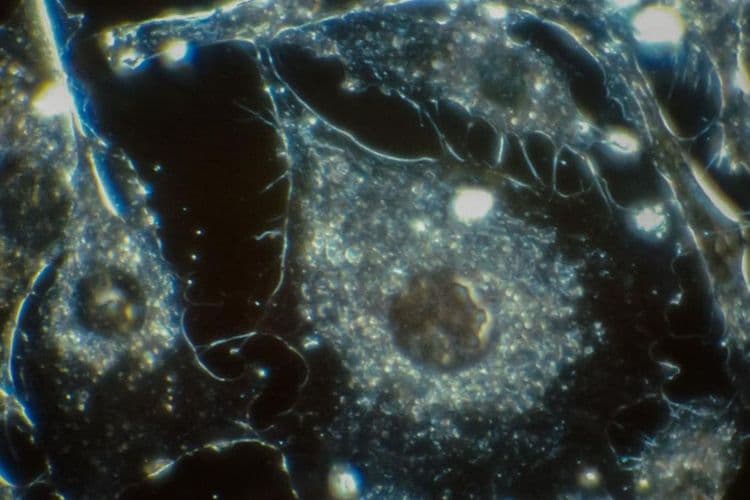

Sidebar: A quick look at the mouth microbiome

- After the gut, the mouth has the second largest and most diverse microbiota.

- Oral microorganisms include bacteria, fungi, viruses, and protozoa.

- Different bacteria populate different areas of the oral cavity.

- Every individual has a unique oral microbiome.

- Mouth microbes tend to work in teams.